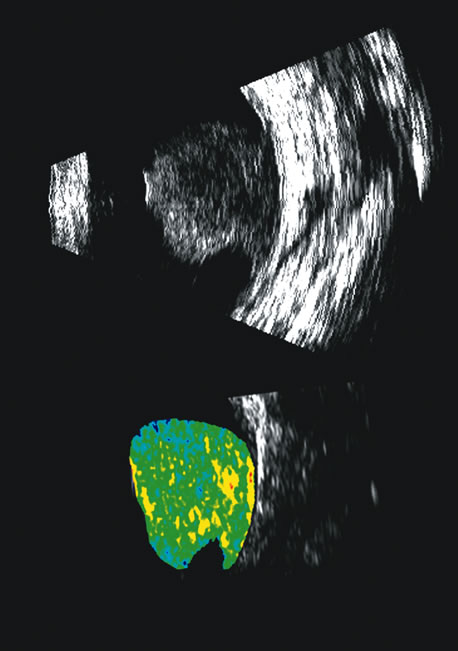

Fig. 25. A 3D reconstruction of serial scans of a posterior pole melanoma taken with a 10 MHz transducer (left) shows the extent and relative asymmetry of the tumor within the vitreous cavity. 3D biometry can be useful for treatment planning for radiotherapy and brachytherapy. 3D reconstructions of 50 MHz serial ultrasound scans and parameter images of a melanoma involving the ciliary body and anterior uvea (center, right) before and after treatment with combined ultrasound hyperthermia and brachytherapy. Changes in the concentration of ultrasound scattering elements related to tissue necrosis are seen as color scale in the pre- and postimage region of the tumor shifts, from blue, indicating relatively low acoustic concentration, to yellow and green, indicating higher concentrations of scatterers.

Spectral parameter imaging, a digital signal processing technique that examines the frequency content of backscattered ultrasound signals, has been shown to be predictive of increased lethality in certain patients and also to be useful in the in-vivo identification of high-risk melanomas for treatment staging.46–48 The shape, density, orientation, and number of scattering elements in a region influence not only the relative amplitude or brightness of a pixel on B-scan but the frequency content of the signal returned to the transducer.19 The concept of differentiating tissue backscatter in a quantitative manner rather than in simple qualitative descriptions of hypo-, iso-, and hyperechoic variations in gray scale allows for maximum use of information available in the digital ultrasonograms. These techniques can be extended to examining the functional anatomy of the eye as well as disease states other than solid tumors (Fig. 26).